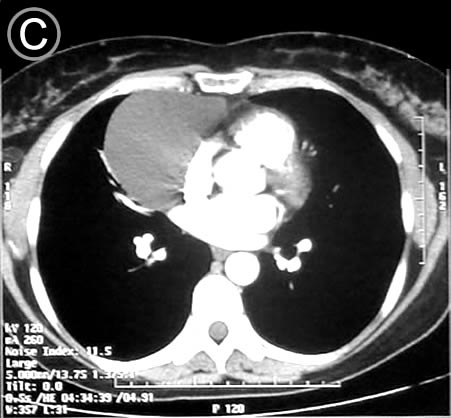

Corte Tomografico C

Corte Tomográfico C

Sección transversal mas bajo, a la altura de los hilios pulmonares y los grandes vasos:

La lesión redondeada en su mayor diámetro, su forma se adapta al continente, hay compresión discreta del pulmón con atelectasia laminar; destaca la homogeneidad de la lesión.